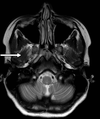

3

Q

A

body of corpus callosum